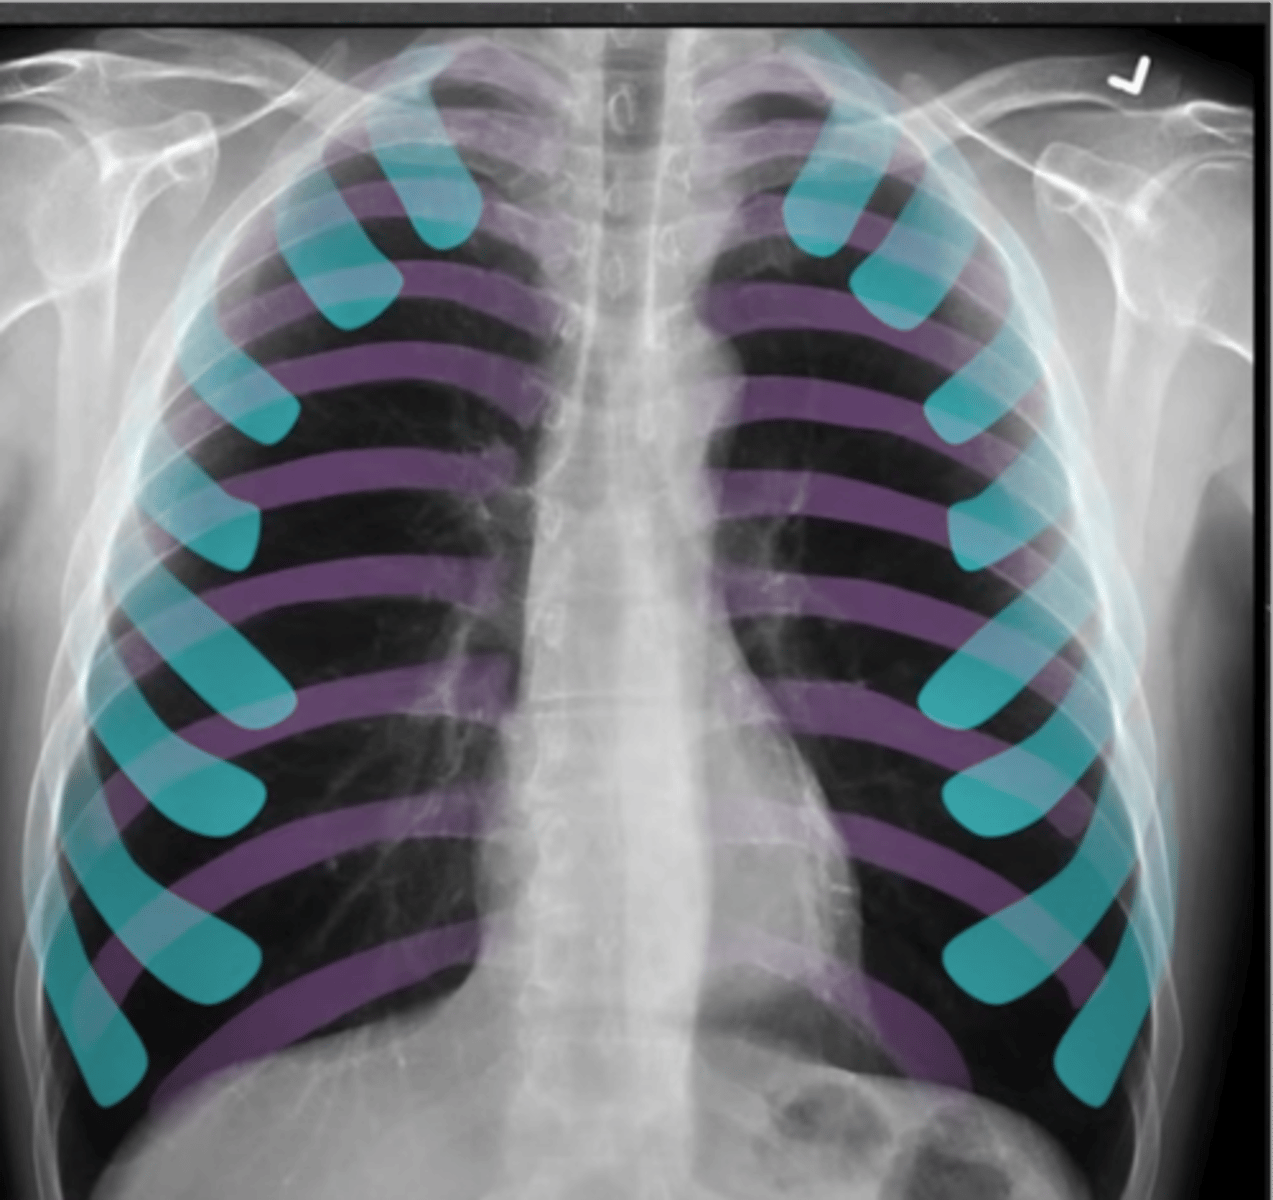

-inspiration: we need good inspiratory effort

-should see 9-10 posterior ribs or 6-7 anterior ribs (7th piercing the diaphragm)

What does the I stand for in RIPE